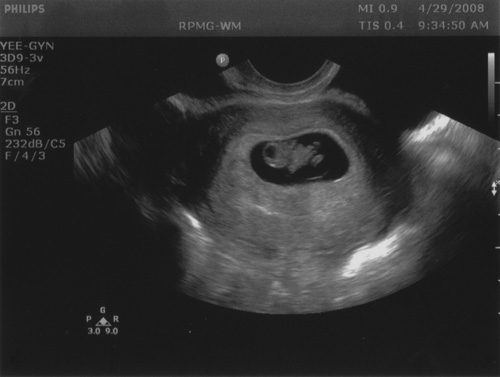

So, the little vaguely-baby-shaped blob that you see in there is our embryo! As Linda mentioned, today was our last scheduled visit to Reproductive Partners, and the picture above is the result.

Before anyone has any illusions otherwise, the picture is actually to-scale on my screen: the entire embryo is 18 millimeters right now, “head” to “toe”. There was definitely a lot more observable now since two weeks ago — for one, Linda could see the heartbeat quite well this time. Plus there’s a clear head, and some appendages: if the ultrasound resolution was higher, we’d be able to see that the fingers aren’t separated quite yet and the hands are still webbed.

As we were leaving the office, a nurse printed a couple of copies of the snapshot that you see above, and pointed out that the black spot near the “head” is a place where the brain will go! Apparently it kind of grows into the space left for it! I found this completely fascinating.